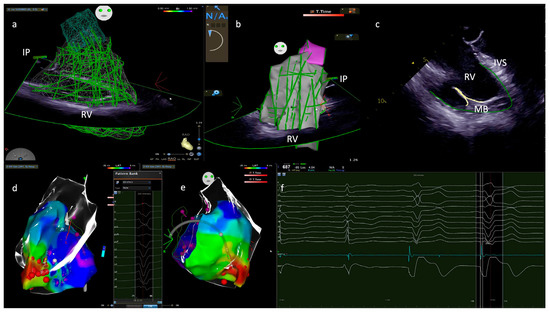

5. Diagnostic of Moderator Band Related Tachycardia

6.1. Ablation Targets